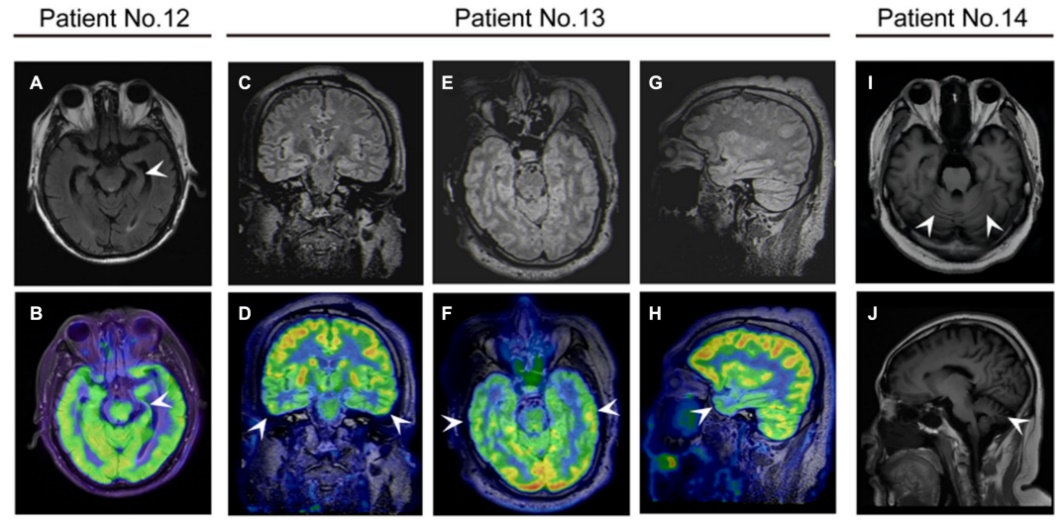

42.9%µÄ»¼ÕßÓÐMRIÒì³££¬£¬£¬£¬£¬£¬£¬£¬°üÀ¨Æ¤ÖÊÔöÇ¿¡¢°×Öʸı䡢º£ÂíÖ×ÕÍ»òήËõÒÔ¼°Ð¡ÄÔήËõ¡£¡£¡£¡£¡£2Àý»¼Õß18F-FDG PET/MRIÌåÏÖΪò¨Ò¶¼°ÇðÄԵʹúл£¬£¬£¬£¬£¬£¬£¬£¬Ó뻼ÕßÁÙ´²Ö¢×´Ò»Ö¡£¡£¡£¡£¡£¿£¿£¿£¿£¿£¿¹DPPX¿¹ÌåÄÔÑ×»¼ÕßMRI¶àÎÞÌØÒìÐÔ [5]£¬£¬£¬£¬£¬£¬£¬£¬18F¡ªFDG PET¶ÔÃ÷È·¿¹DPPX¿¹ÌåÄÔÑ×ÂÄÚ´úлģʽ¡¢Ìá¸ßÑôÐÔ¼ì³öÂÊ¿ÉÄÜÓÐËù×ÊÖú[2]¡£¡£¡£¡£¡£

¿¹DPPXÄÔÑ×»¼ÕßµÄÉñ¾Ó°ÏñѧÌåÏÖ¡£¡£¡£¡£¡£(A£¬£¬£¬£¬£¬£¬£¬£¬B)12ÀýÈÏÖªÕϰ»¼ÕߴʲÕñ³ÉÏñ(MRI)ÏÔʾ×ó²àº£ÂíήËõ£¬£¬£¬£¬£¬£¬£¬£¬Õýµç×Ó·¢Éä¶Ï²ãɨÃèÏÔʾ×ó²àº£Âí18F-·úÍÑÑõÆÏÌÑÌÇ(FDG)ÉãÈ¡ïÔÌ(Õýµç×Ó·¢Éä¶Ï²ãɨÃè)/ºË´Å¹²Õñ³ÉÏñ¡£¡£¡£¡£¡£13ÀýÈÏÖª¹¦Ð§Õϰ»¼ÕßÔÚPET/MRI¹Ú״λ(E£¬£¬£¬£¬£¬£¬£¬£¬F)ÖáλºÍʸ״λ(G£¬£¬£¬£¬£¬£¬£¬£¬H)ÏÔʾ˫²àò¨Ò¶1¡ãF-FDGÉãÈ¡ïÔÌ¡£¡£¡£¡£¡£(1,J)¹²¼Ãʧµ÷»¼Õß14ÀýMRIÏÔʾСÄÔήËõ¡£¡£¡£¡£¡£